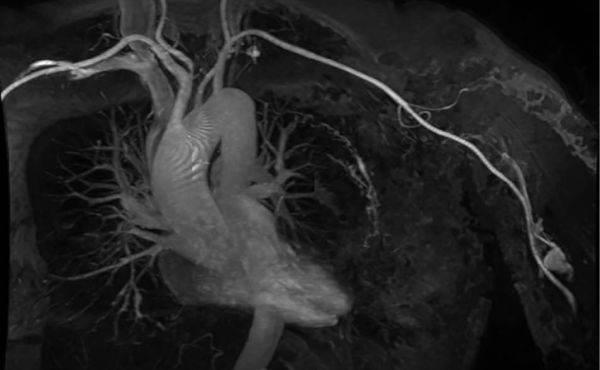

Laparoskopische Cholezystektomie für symptomatische Cholezystolithiasis (CCL) bei „Kasabach-Merritt-Syndrom“ (KMS)